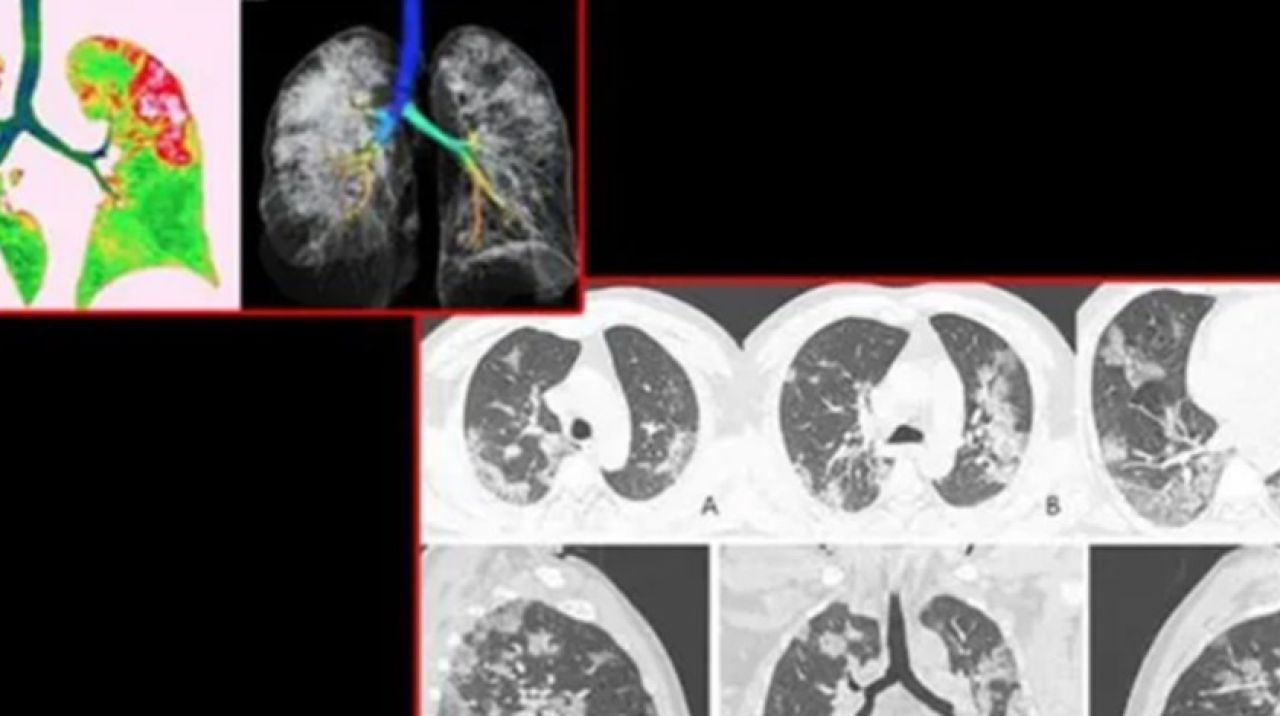

ABD'de bulunan Kuzey Amerika Radyoloji Topluluğu tarafından paylaşılan röntgen görüntüleri koronavirüsünün ciğerlere nasıl etki ettiğini gözler önüne serdi. Uluslararası basın kuruluşlarına yansıyan görüntülerde Wuhan'daki deniz ürünleri pazarında çalışan 44 yaşındaki bir coronavirüs hastasının ciğerlerindeki doluluk oranı görülüyor.

Yapılan açıklamada röntgeni çekilen 44 yaşındaki hastanın 25 Aralık 2019'da hastaneye öksürük ve yüksek ateş dolayısıyla gittiği ve tedavi altına alındığı belirtildi. Yetkililer doktorların müdahalesine rağmen hastanın bir hafta sonra öldüğünü aktardı.